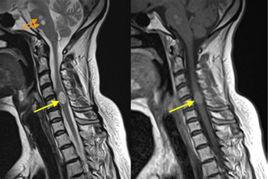

MRI能夠較為全面觀察脊柱的情況,可以確定脊柱轉移瘤的多發病灶,可以說是對脊柱腫瘤最為準確的檢查手段。特別是近年來發展的短T反轉恢復序列(shortTinversionrecovery,STIR)和快速脂肪抑脂自旋迴波序列(fat-suppressedfastspinecho,FSE)的套用,可以更為可靠地觀察腫瘤內組織的特點,有助於在活檢前確定某些類型腫瘤的性質。

MRI檢查:早期有骨髓浸潤現象,脊椎骨質受損、骨轉移、壓縮性骨折、軟組織腫塊、椎管內脊髓病變等,即行SE序列矢狀位T1WI、FSE/TSE矢狀位T2W1、軸位FSE/TSET2W序列。